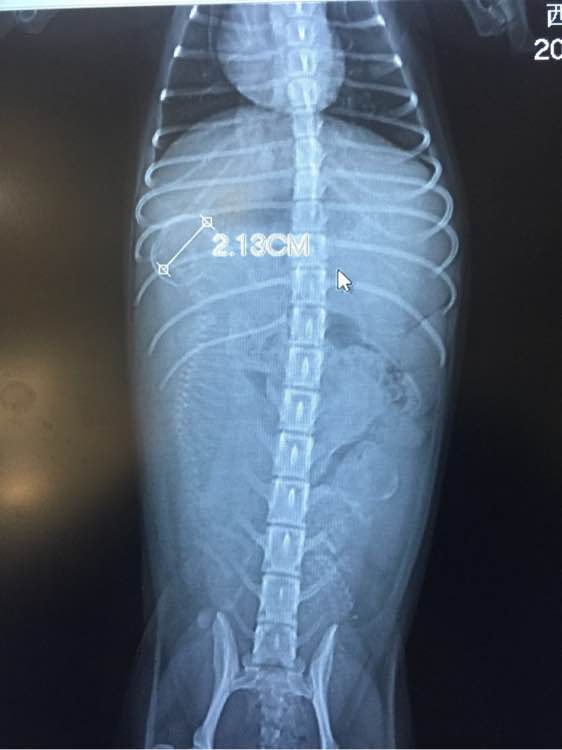

医生拍了片之后,告诉我说,小包子的说不敢再补了,小狗狗一个发育过好,一个发育不良,会影响发育不良狗宝宝的生命安全,医生嘱咐往后的日子不能给狗狗没事加鸡胸肉或者鸡蛋了!要老老实实的吃狗粮了~

刚刚医生把小狗狗的头围发给我了!我感觉是个大头宝宝,会不会难产,每天都很焦虑~